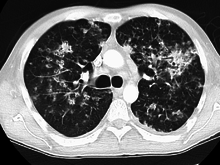

| Chest X ray showing miliary tuberculosis | |

Miliary tuberculosis is a form of tuberculosis that is characterized by a wide dissemination into the human body and by the tiny size of the lesions (1–5 mm). Its name comes from a distinctive pattern seen on a chest radiograph of many tiny spots distributed throughout the lung fields with the appearance similar to millet seeds—thus the term "miliary" tuberculosis. Miliary TB may infect any number of organs, including the lungs, liver, and spleen.[2] Miliary tuberculosis is present in about 2% of all reported cases of tuberculosis and accounts for up to 20% of all extra-pulmonary tuberculosis cases.[3]

Testing for miliary tuberculosis is conducted in a similar manner as for other forms of tuberculosis, although a number of tests must be conducted on a patient to confirm diagnosis.[5] Tests include chest x-ray, sputum culture, bronchoscopy, open lung biopsy, head CT/MRI, blood cultures, fundoscopy, and electrocardiography.[11] The tuberculosis (TB) blood test, also called an Interferon Gamma Release Assay or IGRA, is a way to diagnose latent TB. A variety of neurological complications have been noted in miliary tuberculosis patients—tuberculous meningitis and cerebral tuberculomas being the most frequent. However, a majority of patients improve following antituberculous treatment. Rarely lymphangitic spread of lung cancer could mimic miliary pattern of tuberculosis on regular chest X-ray. [16]